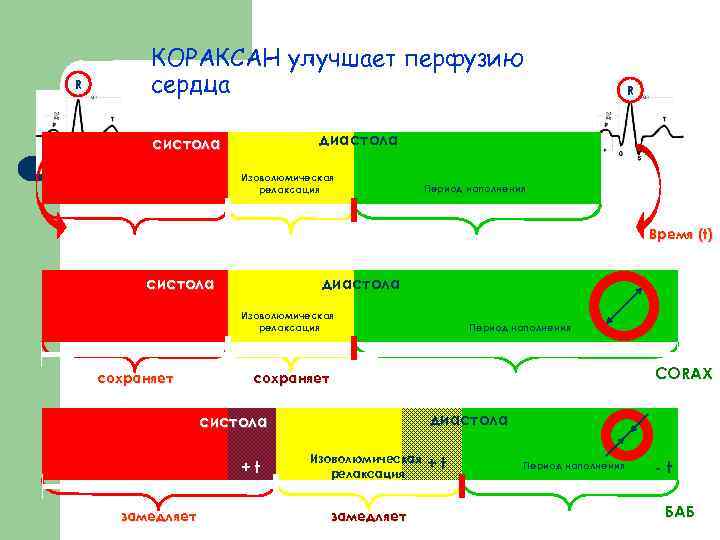

R КОРАКСАН улучшает перфузию сердца R диастола систола Изоволюмическая релаксация Период наполнения Время (t) систола диастола Изоволюмическая релаксация сохраняет CORAX сохраняет диастола систола +t замедляет Период наполнения Изоволюмическая релаксация замедляет +t Период наполнения -t БАБ